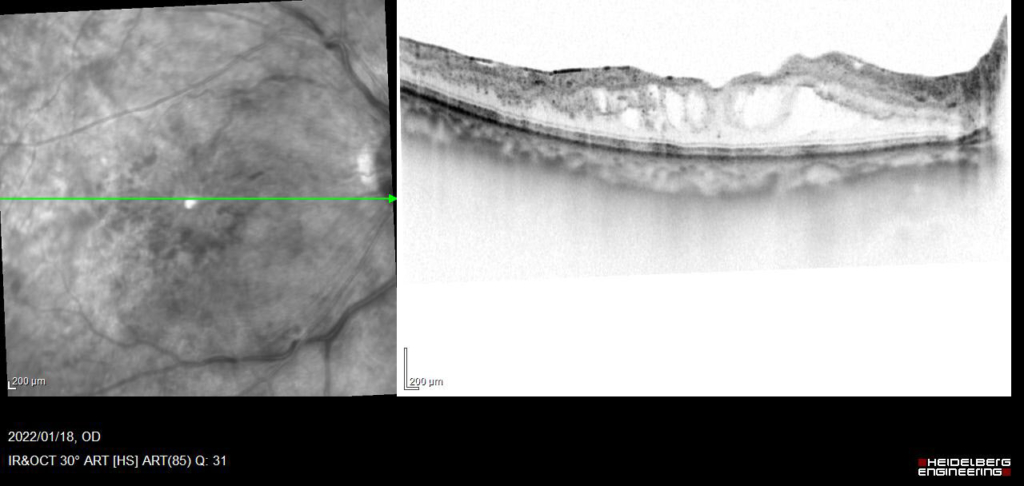

約4か月 抗VGEF(ラニビズマブ)の硝子体注射4回施行後、黄斑浮腫は注射直後に一時的に改善するが、4wで黄斑浮腫は著明に再発する。

アフリベルセプトに変更し、PRP施行。

発症後約6か月後